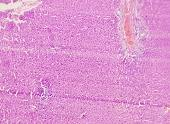

All the animals were observed daily for clinical signs of toxicity and morbidity. Individual animal body weights were recorded at receipt (on day 1) and weekly thereafter and at the time of sacrifice (fasting body weights). Histological examinations of various organs (brain, kidney, liver, small intestine and stomach) were carried out after 28 d using haematoxylin and eosin as staining agents. The organs were preserved in 10 % formalin solution.

On administration of TPSY, the animals in all groups were found to survive at the end of 28 d of study. The histological results are shown in table 4. Liver tissue showed minimal degeneration of hepatocytes compared to control at the highest dose of 350 mg which was however reported to be non-toxic.

Mild tubular degeneration was observed in kidneys Stomach tissue displayed moderate changes compared to control, with minimal degeneration of mucosal cellsat highest dose of 350 mg. Large intestine showed marked submucosal edema but the mucosal tissue appeared to be normal at the highest dose of 350 mg. No abnormality was observed in brain tissues at a low and medium dose. Mild submucosal edema was observed at 350 mg/kg. These results point to the negligible toxicity associated with the thiolated polymer and hence it can be considered to be safe for use as a pharmaceutical excipient.

Table 4: Histological results of repeated dose toxicity studies of TPSY (n=5)

| Organs | Normal saline | TPSY dose strength | ||

| Control | 70 mg/kg | 175 mg/kg | 350 mg/kg | |

| Liver | Normal architecture of liver, nothing abnormal detected. | Nothing abnormal detected. | Minimal degeneration of hepatocytes. | Minimal degeneration of hepatocyte and infiltration of inflammatory cells. |

| Kidney | Normal architecture of kidney, nothing abnormal detected. | Minimal tubular degeneration. | Mild tubular degeneration and congestion of blood vessels. | Mild tubular degeneration. |

| Stomach | Normal architecture of Stomach, Nothing abnormal detected. | Minimal degeneration of mucosal lining cells. | Mucosal cells were enlarged and were darkly stained. | Minimal degeneration of mucosal cells, accumulation of dark staining material in the gland. |

| Brain | Normal architecture of the brain, Nothing abnormal detected. | Nothing abnormal detected. | Nothing abnormal detected. | Minimal neuronal degeneration. |

| Large intestine | Papillary projections with goblet cells. | Mucosal lining no infiltration of inflammatory cells. | Minimal infiltration of inflammatory cells and congestion. | Marked submucosal edema, mucosal tissue appears normal. |

![]() |

| A: Liver (Control) | B: Liver (350 mg/kg dose) |

| C: Kidney (Control) | D: Kidney (350 mg/kg dose) |

| E: Stomach (Control) | F: Stomach (350 mg/kg dose) |

| G: Brain (Control) | H: Brain (350 mg/kg dose) |

| I: Large Intestine (Control) | J: Large Intestine (350 mg/kg dose) |

Fig. 8: Histology of various tissues at highest dose strength of 350 mg/kg body weight